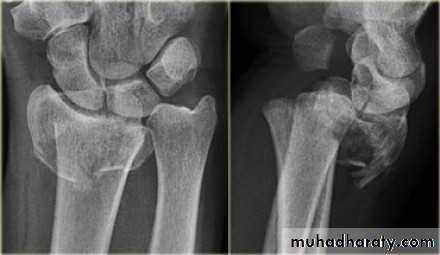

Upper limb

Fall on out stretched hand

Possible complications

Fracture

Ass n injury